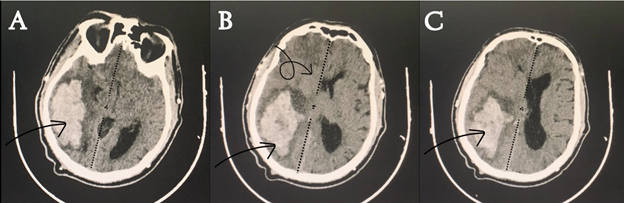

A 55-year-old male, diagnosed with end-stage renal disease (ESRD) and hypertension, was urgently transported to the emergency department due to the sudden onset of a severe headache. This incapacitating headache, which occurred in a relaxed, non-strenuous setting, was accompanied by recurrent episodes of vomiting and rapidly progressed to a state of confusion. Additionally, the patient reported experiencing eye pain and blurred vision immediately following the onset of this distressing episode. This intricate clinical presentation is compounded by the patient's extensive medical history, including a 15-year battle with diabetes mellitus (DM), further complicated by diabetic nephropathy and retinopathy over the past 5 years. Moreover, the patient has been managing hypertension for 6 years, necessitating ongoing antihypertensive medications. 5 years ago, the diagnosis of end-stage renal disease was established, leading to the initiation of a maintained hemodialysis regimen. Upon arrival, the patient exhibited generally stable vital signs, except for a notable blood pressure reading of 210/100 mm Hg. Although the Glasgow Coma Scale (GCS) indicated a score of 14 out of 15, suggestive of relatively preserved consciousness, the patient was notably unable to articulate speech. This condition further deteriorated to a GCS score of four out of 15, necessitating immediate surgical intervention. During the chest examination, bilateral decreased air entry was evident, with a more pronounced reduction noted on the left side. On further neurological assessment, the patient presented with a striking clinical finding: left-sided paraplegia, indicating impaired motor function in the lower limbs. A non-contrast brain CT scan revealed a hyperdense lesion on the right side of the brain, consistent with intraparenchymal hemorrhage (Figure 1). This hemorrhagic region was accompanied by a significant midline shift measuring approximately 9 millimeters, indicative of the displacement of brain structures toward the opposite side due to the intracranial hemorrhage.

Figure 1 Non-contrast preoperative brain CT scan depicting right intraparenchymal hemorrhage and evident midline shift.(A-C): different levels of brain CT scam showing the size and extent of the ICH.